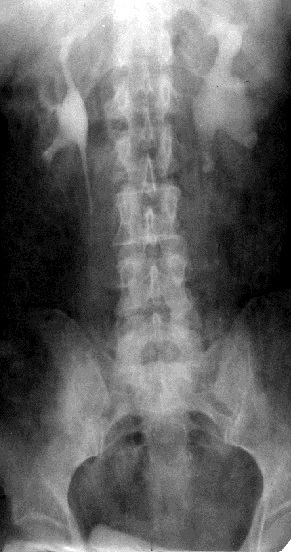

Анализ лучевых исследований внутренних органов обычно проводится по такой схеме:

1. Метод исследования.

2. Анатомическая область или орган исследования

2. Проекция исследования.

3. Локализация очагов поражения.

4. Количество очагов поражения.

5. Характер тенеобразования.

6. Структура очага поражения.

7. Форма очага поражения.

8. Размеры очага поражения.

9. Контуры очага поражения.

10. Состояние окружающих органов и тканей.

11. Ведущий синдром.

12. Его морфологический субстрат.

На первые три вопроса Вы научились отвечать на первом занятии. Для определения локализации очагов поражения необходимо использовать все свои знания по анатомии человека.